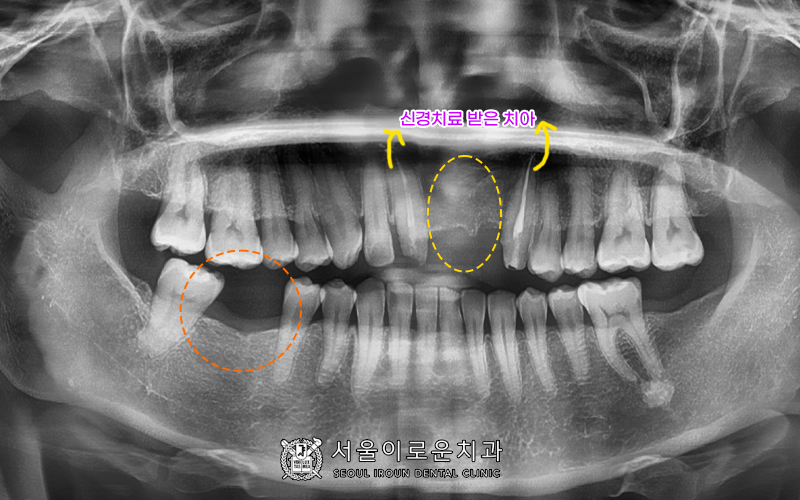

큰 앞니와 송곳니를 보시면

이전에 신경치료를 받으신 상태인 것을

알 수 있는데요.

임상증상이 없는 건전한 상태셨으나,

다음과 같은 경우, 치아를 상실했을 때

임플란트로 빈공간을 채우는 것이

일반적이지만, 환.자분처럼 현재 임플란트가 어렵고

이미 과거에 브릿지 치료를 받으셨던

상태에서는 브릿지 치료가 더욱 심미적이고

좋은 치료결과를 기대할 수 있습니다. ^^